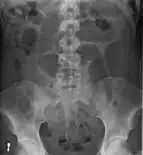

- Abdominal x-ray – tire-like shadow arising from right iliac fossa and passing to left

Plain X ray of a cecal volvulus

CT scan of a cecal volvulus